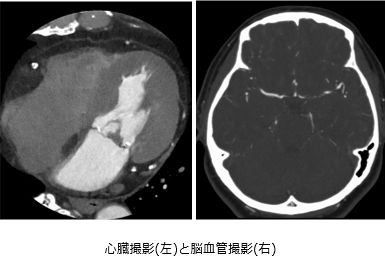

CT22.png CT23.png

いろいろな断面を撮影することができるため、

骨や臓器などの状態を詳しく見る事ができます。

造影剤を使用することで、臓器や血管の構造などを

より詳細に把握することができます。